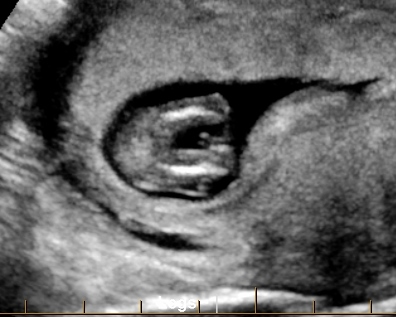

Guesses anyone? Was told boy at 12w2dAttachment 18706Attachment 18707Attachment 18708

Poss girl but not sure that's the nub?!?

I don't see a nub. How many weeks are you?

12w2d

Too early for a potty shot, and I don't see a nub. But I don't see anything obvious in the potty shot, so slight girl lean.

No nub, can't go by potty shot.